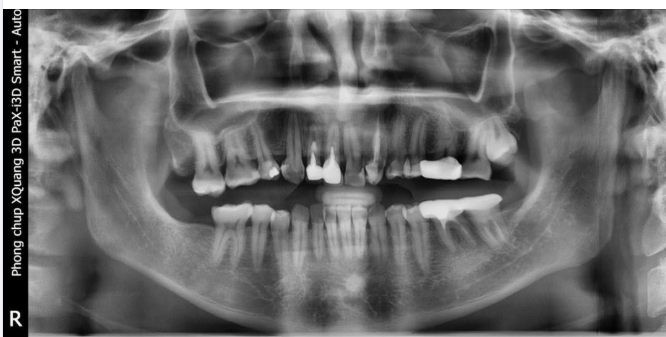

HẬU QUẢ CỦA VIỆC TRÌ HOÃN KHÔI PHỤC RĂNG MẤT